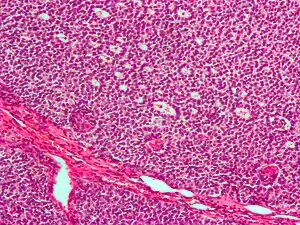

| Micrograph of a granulosa cell tumour, a type of sex-cord–gonadal stromal tumour. H&E stain. | |

Low magnification micrograph of a granulosa cell tumour. H&E stain.